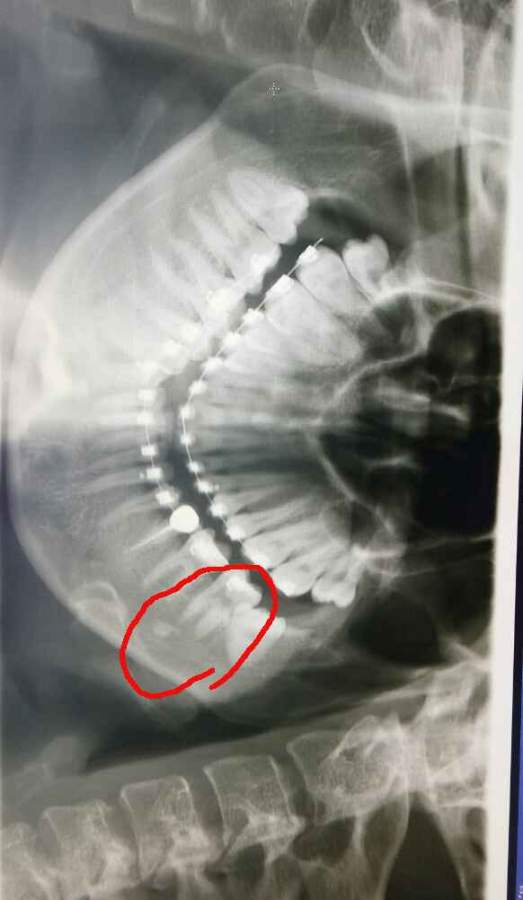

请问谁知道?牙齿下面的一块白的是什么?拍了好多次照片,每次都有。 发自小木虫Android客户端 |